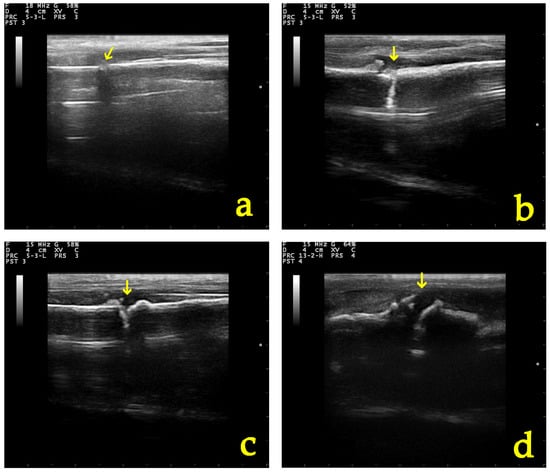

3.5.1. Ultrasonographic Examination

| Parameter of Ultrasonographic Examination | Group | D0 | D5 | D10 | D20 | D28 |

|---|---|---|---|---|---|---|

| Echogenicity and structural organization of the tissue at the fracture site | A | 1 (1–1) | 2 (1–2) | 2 (2–2) | 3 (3–4) | 3.5 (3–4) |

| B | 1 (1–1) | 1 (1–2) | 2 (2–2) | 3 (2–4) | 4 (2–4) | |

| Formation of the callus and the vascularization present at the osteotomy | A | 1 (1–1) | 2 (2–2) | 2 (2–2) | 3 (2–4) | 3.5 (3–4) |

| B | 1 (1–1) | 2 (2–2) | 2 (1–2) | 3 (2–4) | 4 (2–4) | |

| Total grade | A | 1 (1–1) | 1.5 (1–2) | 2 (2–2) | 3 (3–4) | 3.5 (3–4) |

| B | 1 (1–1) | 1 (1–2) | 2 (2–2) | 3 (2–4) | 4 (2–4) |